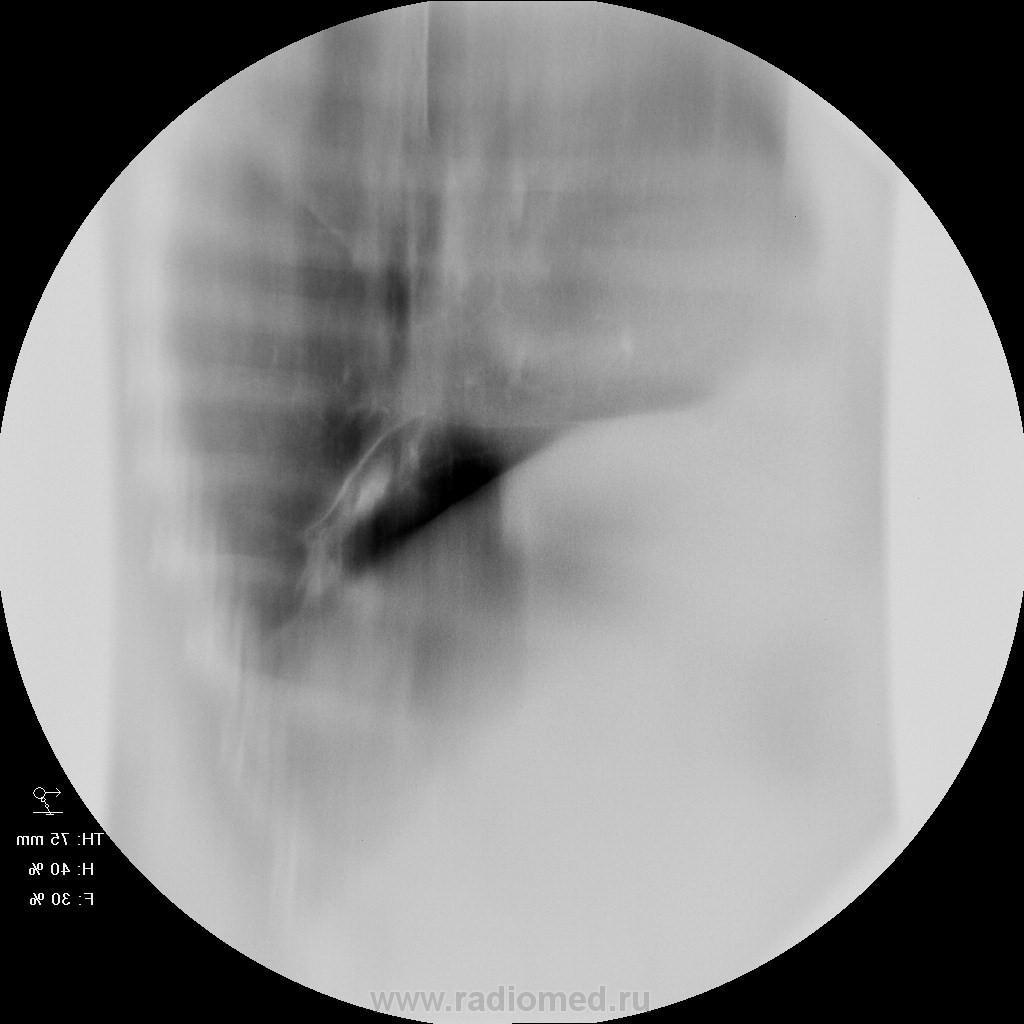

Женщина 50 лет поступила а пульмонологическо отделение с клиникой и диагнозом обострения бронхита. 15 лет назад перенесла тяжелую пневмонию нижней доли правого легкого. после этого находили выше указанные изменения в легих и наблюдали у фтизиатров. со слов " дисковидная туберкулема" или что-то вроде этого. на флю - картина на протяжении всего времени стабильная. на фбс - нижнедолевой бронх для эндоскопа не проходим, контактная кровоточивость, взята биопсия. прошу совета. какие будут мнения? выставляю только томо - снимки обычные не снимал. но картина на них подобная. по анализам без особенностей. не худела...

К своему стыду, первый раз услышал термин "дисковидная туберкулома". По всей видимости, наши коллеги фтизиатры, таким термином "матерят" застарелые, захолонувшие небольшие интерлобарные осумкованные выпоты, которые на "прямой рентгенограмме" могут дать тень типа "фигли-мигли", которые - то и выпотами назвать сложно?

так как обозвать эту линзу с плотностью кальцинта? я вижу ателектаз-гиповентиляцию нижней доли, на фоне чего - эта "линза" - постпнемонический фиброателектаз?

А это не может оказаться обычным бронхолитиазом?

Обычно бронхолитиаз возникает в результате пролежня кальцинированного лимфоузла в корне легкого.

Мне очень импонирует мысль о БРОНХОЛИТИАЗЕ....